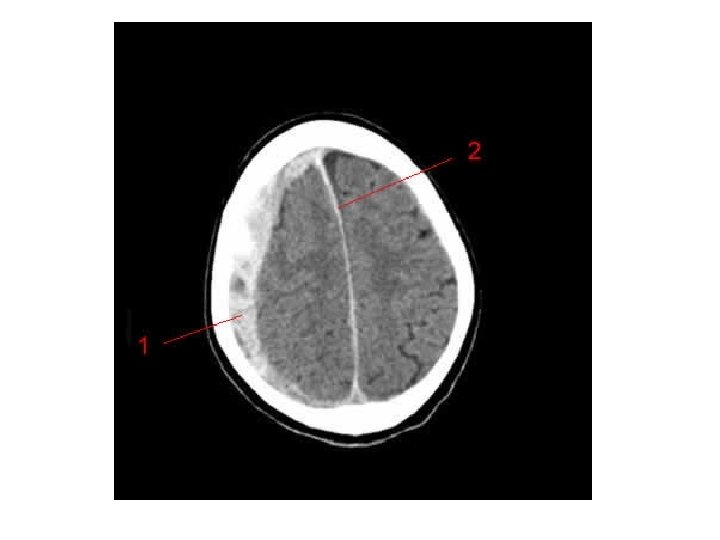

Les différentes lésions 2/2 • Hématome extra-dural – L'hématome extra-dural ou épidural est une accumulation de sang entre l'os du crâne et la dure-mère (enveloppe fibreuse du cerveau faisant partie des méninges). L'hématome extra-dural est une urgence chirurgicale absolue. Il se développe en quelques heures et peut entraîner la mort du patient par engagement cérébral si rien n'est fait. • Hématome sous-dural – Il s'agit d'un épanchement sanguin situé entre, en dehors la dure-mère, et en dedans l’arachnoïde. Il peut survenir de façon aiguë, au cours des heures suivant le traumatisme (hématome sous-dural aigu). Il est alors fréquemment associé à une contusion cérébrale dont peut dépendre le pronostic. Il peut aussi se constituer à bas bruit, et se démasquer quinze jours, voire des semaines après un traumatisme relativement peu important (hématome sous-dural chronique). • Hémorragie intracérébrale – Il s'agit d'un saignement à l'intérieur du parenchyme cérébral. • Hémorragie méningée – Une hémorragie méningée est observée dans 1/3 des traumatismes crâniens sévères. Elle peut être secondaire à la lésion d'un vaisseau méningé, ou bien à une suffusion hémorragique à partir d’un foyer de contusion du cortex cérébral.